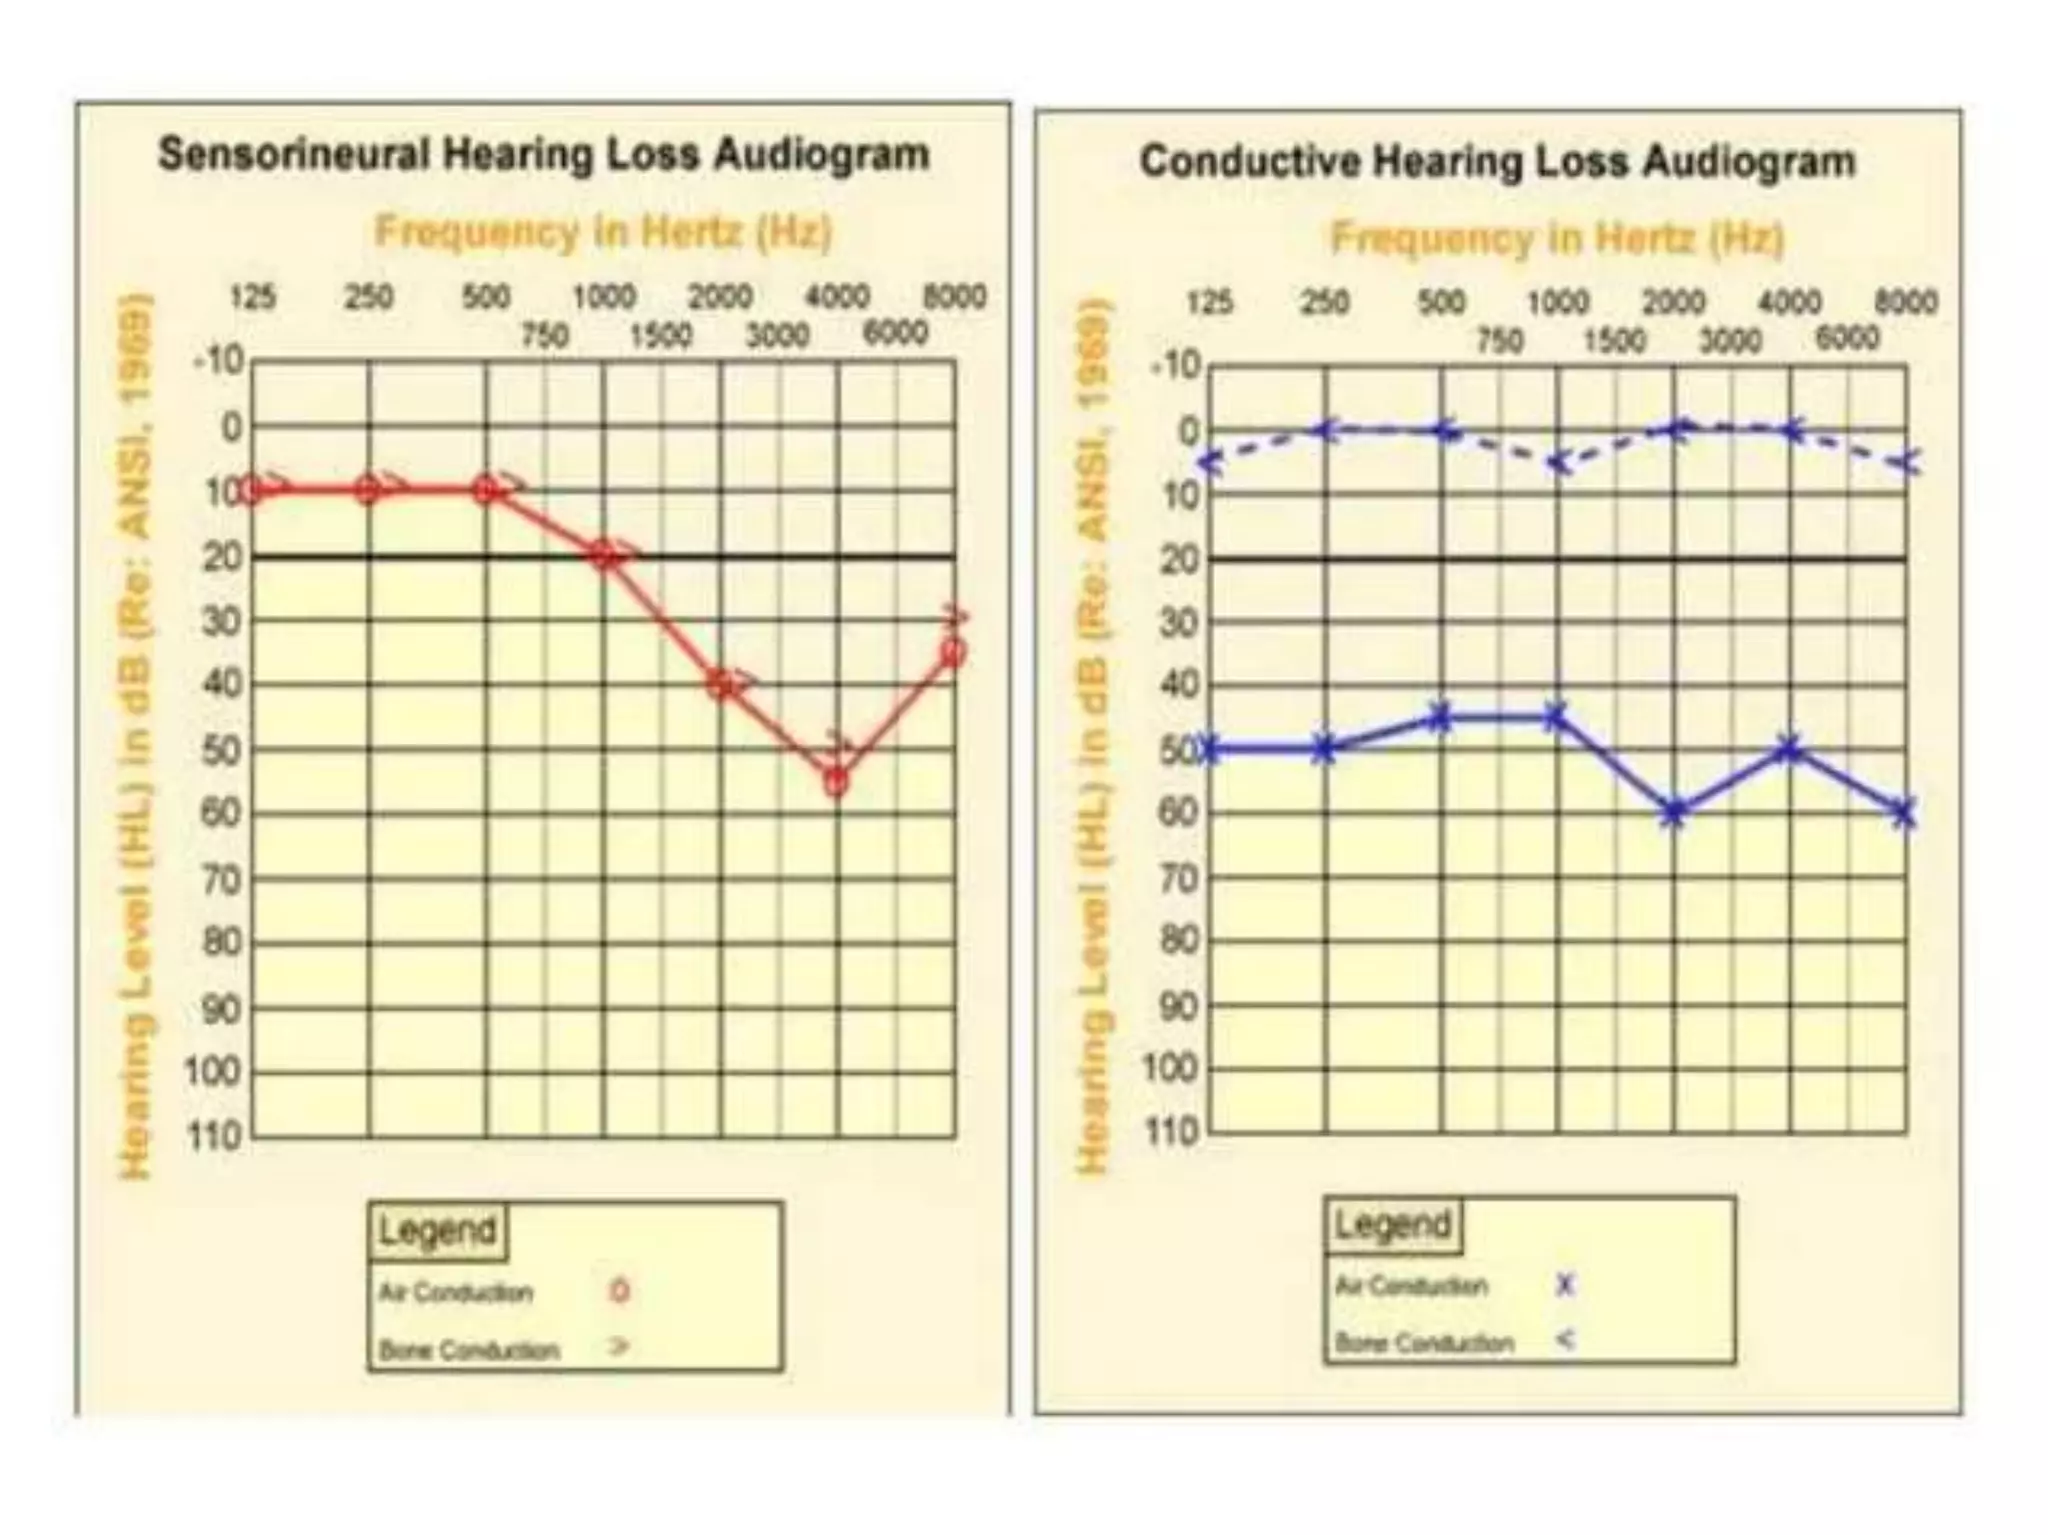

Chronic otitis media is a chronic inflammation of the middle ear and mastoid cavity that presents with recurrent ear discharge through a perforated eardrum. It has several subtypes depending on the state of the eardrum perforation and epithelium. It can be caused by prior acute otitis media, genetics, environment, eustachian tube issues, gastroesophageal reflux disease, craniofacial abnormalities, or immune deficiency.